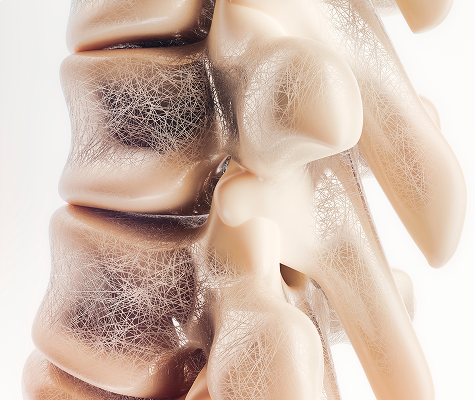

What is Osteoporosis?

Osteoporosis is a condition where bones become weak, brittle, and more likely to fracture. It happens when bone density decreases and the body can’t rebuild bone as quickly as it breaks it down.

Why It Matters:

People with osteoporosis are at higher risk of fractures — especially in the hip, spine, and wrist — even from minor falls or injuries.

Bone Mineral Density (BMD) Scan

Also known as a DEXA scan, this is the gold standard for detecting bone loss.

- Fast, painless, and non-invasive

- Measures bone strength in key areas like the hip and spine

- Provides a T-score to assess your fracture risk